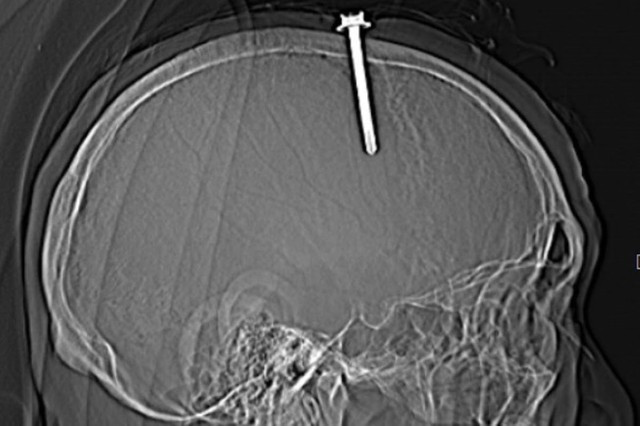

| Hình ảnh cây đinh đâm xuyên vào hộp sọ bệnh nhân. Ảnh: BVĐK Thanh Hóa |

Trước đó, Bệnh viện Đa khoa tỉnh Thanh Hóa tiếp nhận bệnh nhân là L.Q.T. (63 tuổi, nam, ngụ tỉnh Thanh Hóa) nhập viện trong tình trạng bị một cây đinh đâm xuyên hộp sọ, nguy hiểm tới tính mạng.

Qua thăm khám lâm sàng và kết quả chụp cắt lớp vi tính sọ não cho thấy bệnh nhân có vết thương sọ não, vết thương xoang tĩnh mạch dọc trên do dị vật kim loại cắm vào vùng đỉnh bên trái, cạnh xoang tĩnh mạch dọc trên. Dị vật có đường kính 0,5 cm, chiều dài 5,1 cm.